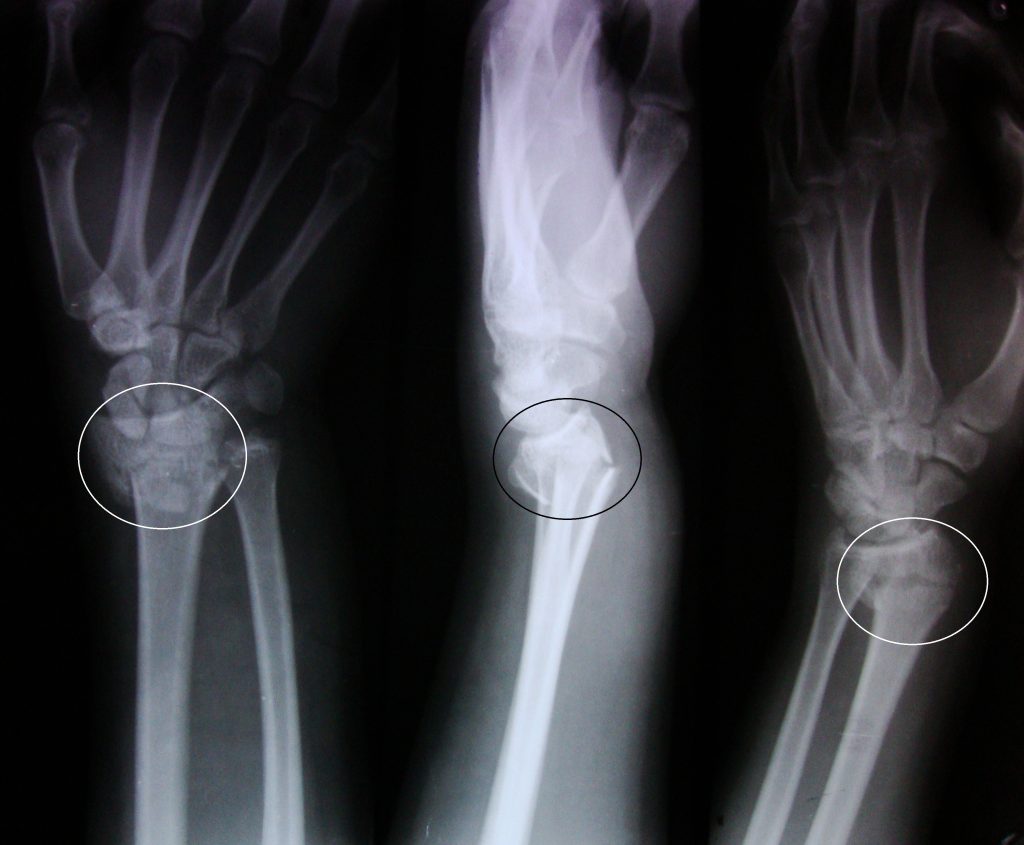

شکستگی استخوان مچ دست ( شکستگی اسمیت ) – (Broken Wrist (Smith Fracture

شکستگی اسمیت نوع خاصی از شکستگی مچ دست است. معمولا زمانی رخ می دهد که فرد با پشت دست می افتد. در این حالت ممکن است درد، تورم و کبودی رخ دهد. ممکن است مچ دست تغییر شکل پیدا کند. درمان فوری اهمیت دارد. شکستگی های درمان نشده ی مچ دست ممکن است آسیب دائمی و درد مزمن ایجاد کند.